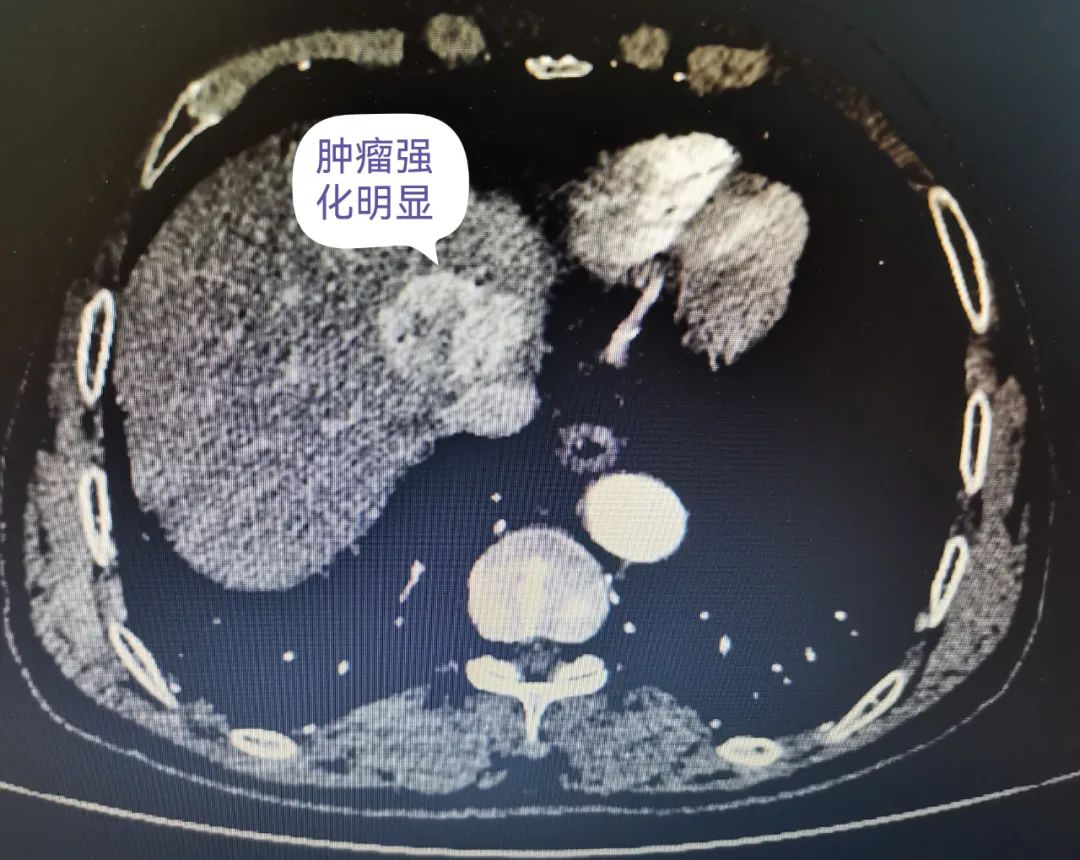

据悉,该患者有乙型肝炎等肝癌高危病史,因腹胀、纳差至我院就诊,完善腹部增强CT提示第二肝门区肝细胞癌(直径约36mm)并肝中静脉侵犯/癌栓形成,肝左叶子灶;查甲胎蛋白 64.1ng/ml。介入血管心脏外科李立涛主任在充分评估患者状况后,申请多学科会诊,诊断为IIIa期肝癌、肝功能A级,决定行D-TACE联合免疫靶向治疗,手术顺利完成,术后患者仅出现轻度腹痛腹胀不适,予对症处理后缓解,后转肿瘤科继续治疗。

术前增强CT提示肿瘤强化明显